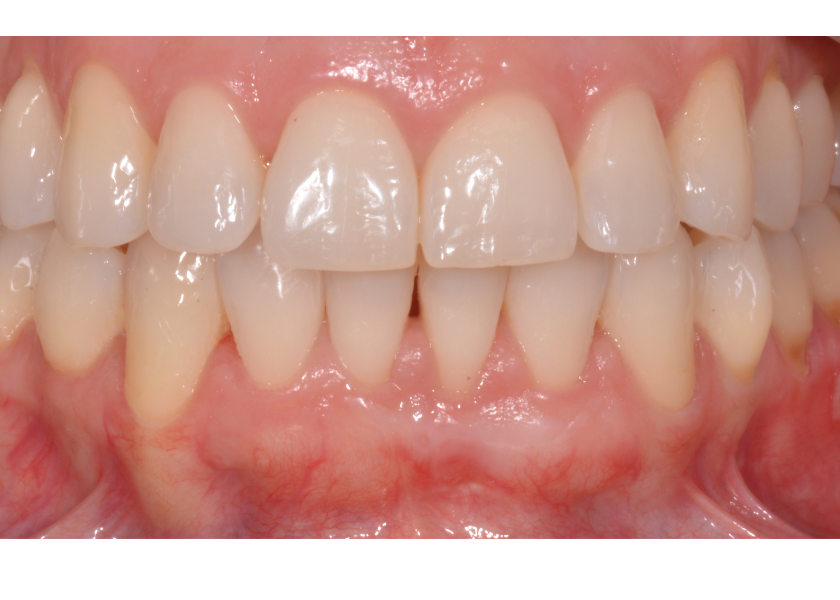

En este caso se decide realizar una cirugía (injerto de tejido conectivo) durante el tratamiento de ortodoncia y seguir moviendo la raíz hacia una posición más favorable dentro de la arcada. Esto se hizo con la intención de cubrir la exposición de la raíz que le estaba provocando sensibilidad y mejorar la encía resultante de los cuatro incisivos inferiores.